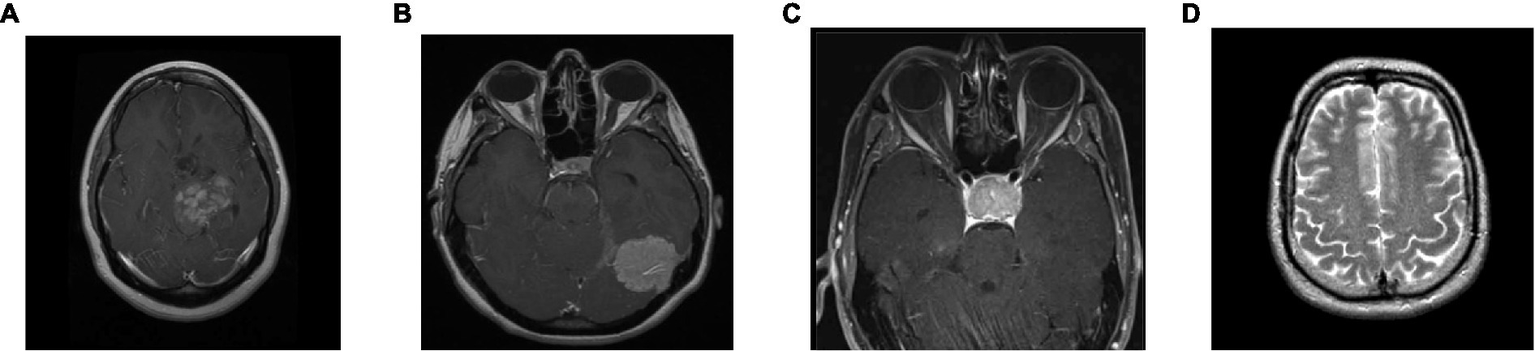

To analyze the presented framework, we consider the two brain MRI image dataset scenarios: binary (healthy vs. pathological) and multiclass (glioma vs. meningioma vs. pituitary). The first scenario comprised 2,376 T2-weighted MRI images, including 1746 pathological (glioma, Sarcoma, meningioma, and Alzheimer’s) and 630 healthy images (Kaggle, n.d.). The second scenario constituted 2,764 T1-weighted contrast-enhanced MRI images with 926 glioma, 937 meningioma, and 901 pituitary gland tumor images (MRI, n.d.). Figure 2 shows the sample images used in this work. All of these images have varied resolution sizes; however, to feed these images to the proposed deep net, we resize them to 224 × 224 × 3.

Figure 2

Sample brain MRI images: (A) glioma; (B) meningioma; (C) pituitary; (D) healthy.